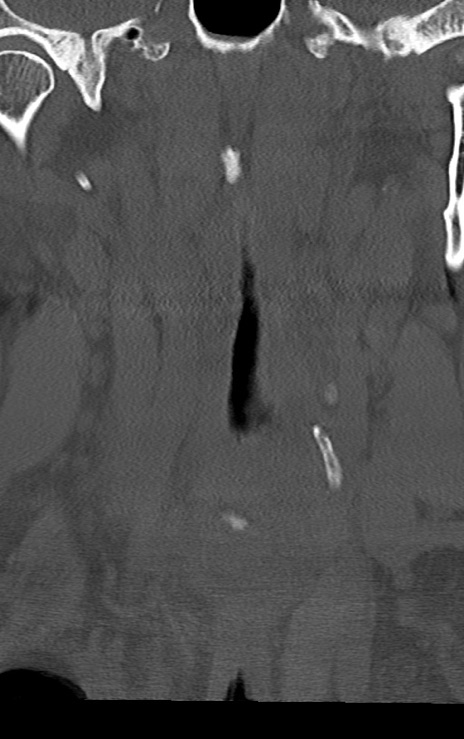

頚椎CT

横断像